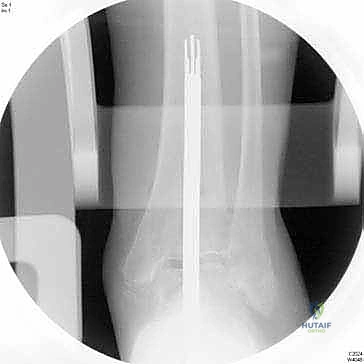

4. إعداد القناة النخاعية وتركيب الساق (Stem)

يتم عمل ثقب دقيق في القناة النخاعية لعظمة الساق. يتم إدخال القطع المعيارية (Modular Stem Pieces) واحدة تلو الأخرى حتى يتم تحقيق التثبيت العميق والمستقر داخل العظم. هذا هو سر قوة نظام INBONE.

6. التحقق والإغلاق

يتم فحص المدى الحركي للكاحل الجديد وثباته تحت جهاز الأشعة السينية (Fluoroscopy) داخل غرفة العمليات للتأكد من المحاذاة المثالية بنسبة 100%. بعد ذلك، يتم إغلاق الشق الجراحي بغرز تجميلية، ووضع جبيرة ناعمة أو حذاء طبي واقٍ.